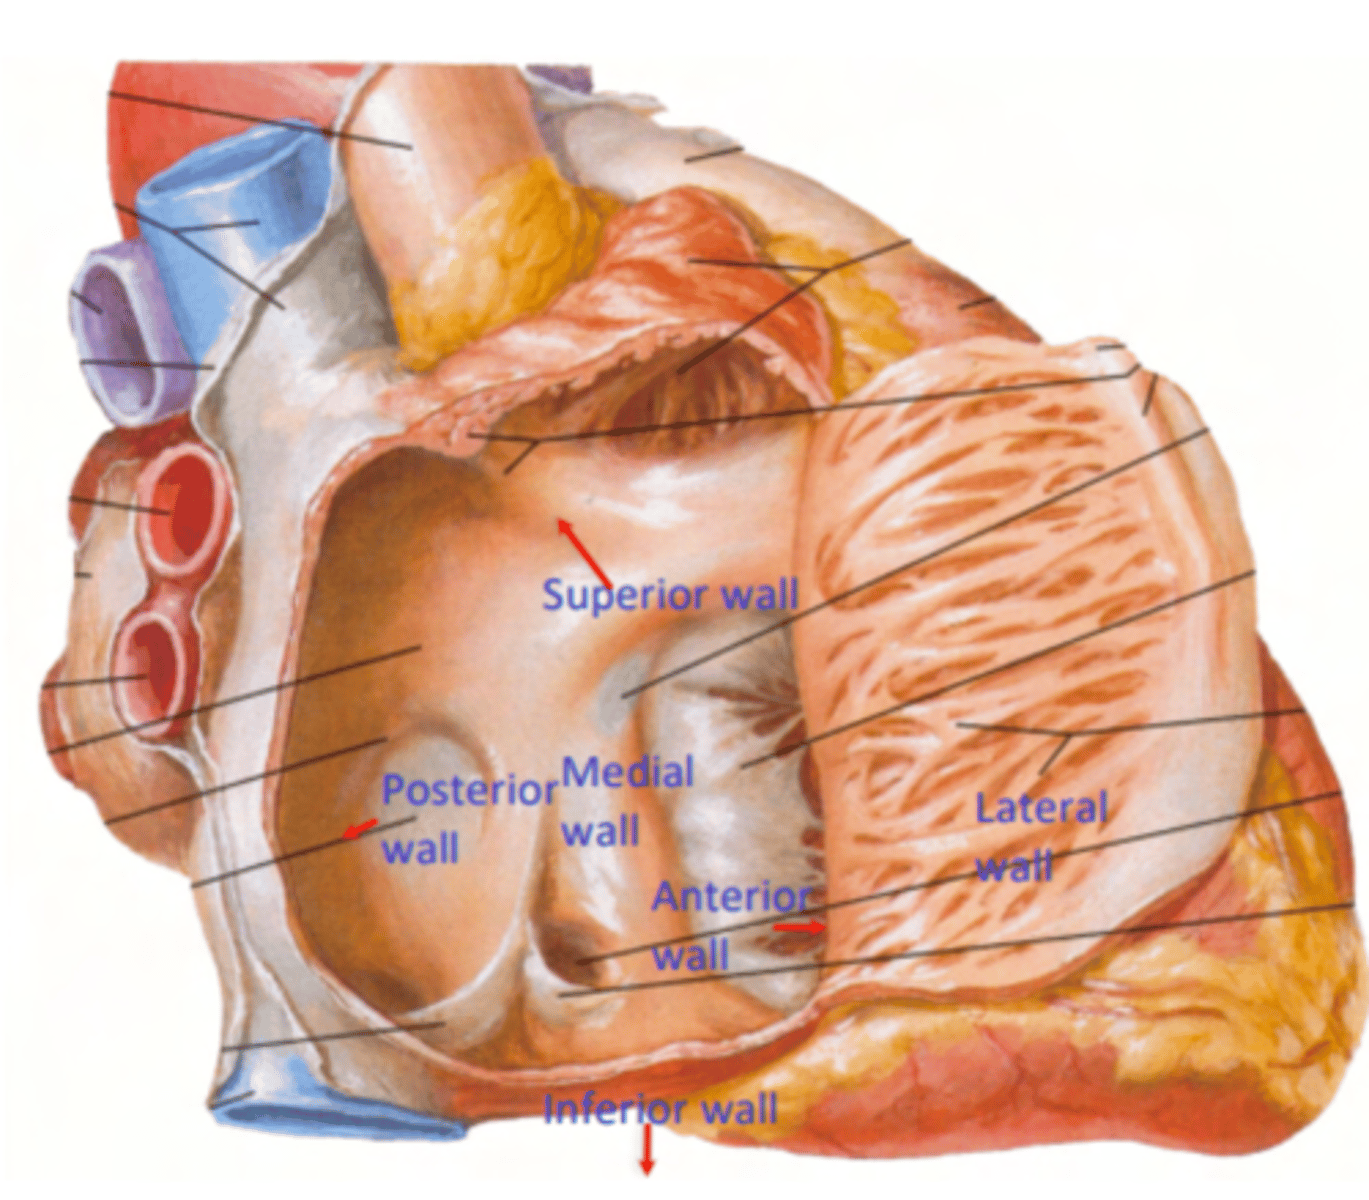

What are the six surfaces that form the internal structure of the right atrium?

. superior

. inferior

. posterior

. medial

. anterior

. lateral walls.

What is the vein entering without valve in the right atrium?

Superior Cava vein

(No valve for entry)

What are the veins entering with valves in the right atrium?

Inferior cava vein (left)

Coronary sinus (right)

Both of them with a valve for entry

What is pointing the blue square?

valves of inferior vena cava and coronary sinus

What is the trabeculated wall in the atrium?

Right Auricle

What are the name of the musculi of the right auricle?

Musculi pectinati

TRABECULATED WALL VS THE SMOOTH INTERIOR PART OF THE ATRIA

What separates the trabeculated from the smooth walls in the atrium?

Crista terminallis

ANATOMICAL LANDMARK indicates the transition between the original embryological parts of the atrium.

What is the remnant of the foramen ovale?

Fossa Ovalis

belongs to the Septum Primum (thinner atrium region)

during fetal live it serves as a passage of blood from let to right